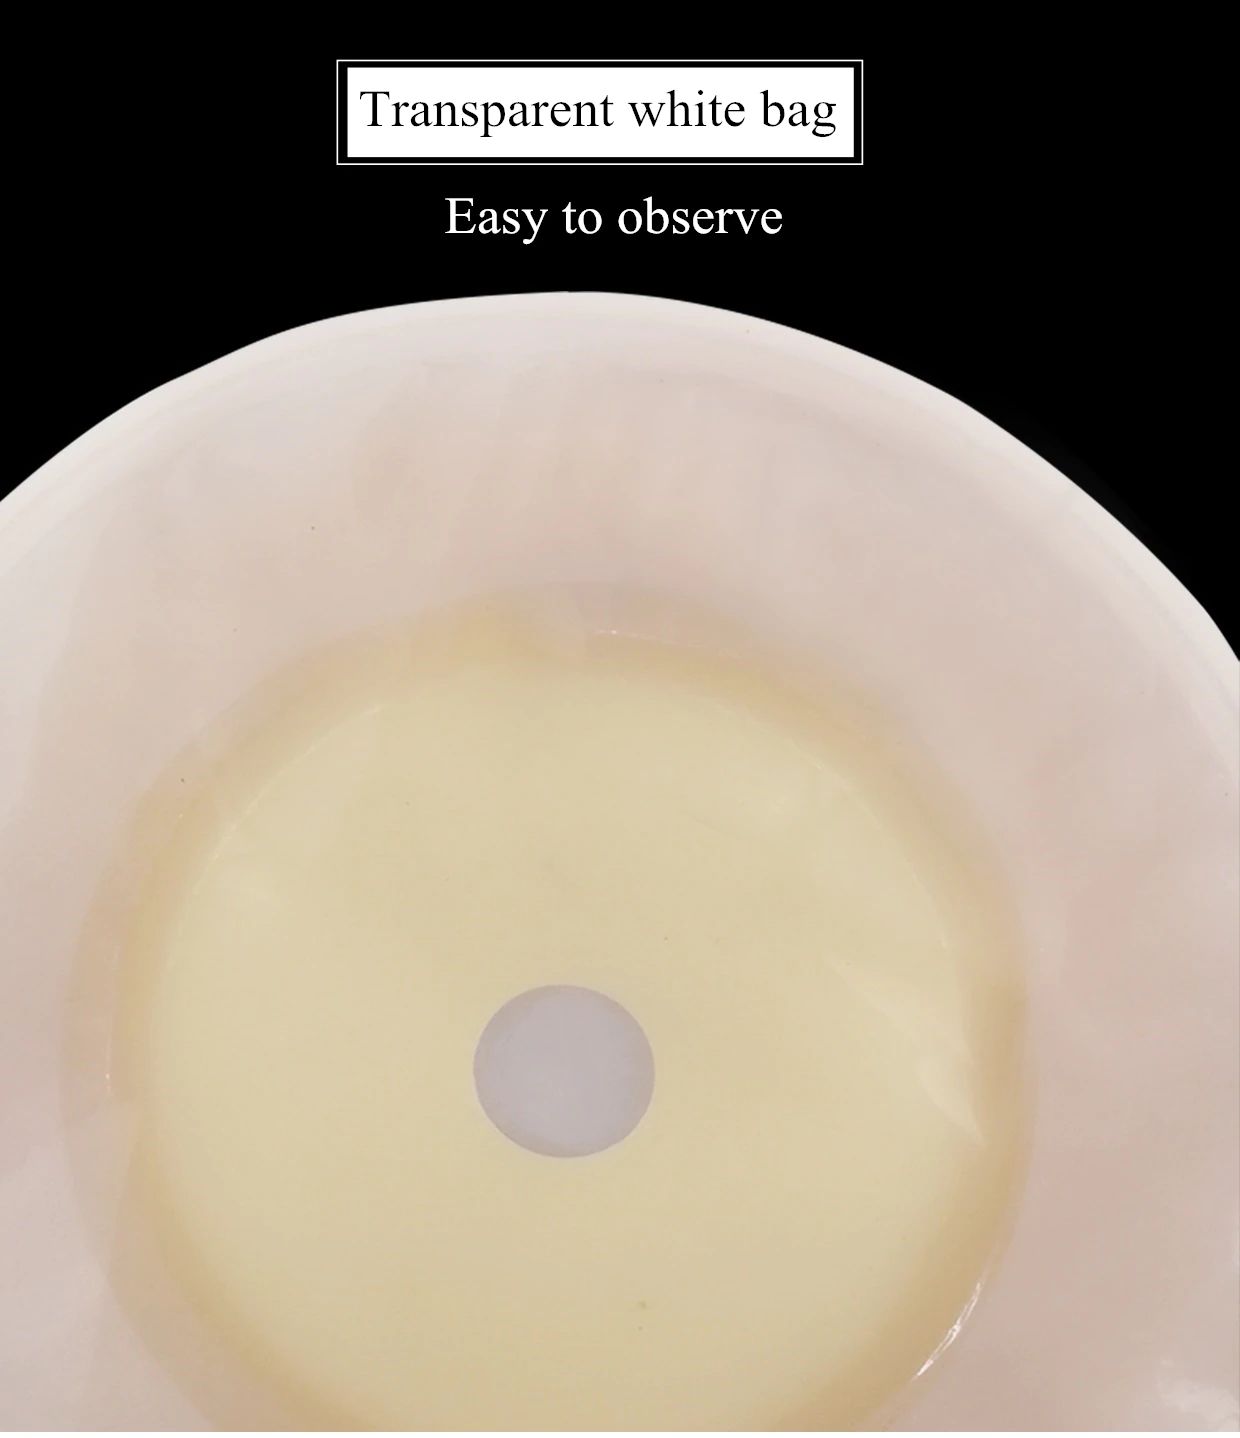

10 Uds. Bolsas de ostomía de sistema de una pieza bolsa de colostomía drenable estoma de ostomía 60mm Tamaño de corte Beige cubierta bolsa de orina con cierre de Clip

Descripción del producto La bolsa de cuidado de ostomía combina la barrera de la piel y la bolsa de colección en un sistema simple y fácil de administrar, proporcionando una gran simplicidad. La bolsa de colostomía es fácil de aplicar con el cierre de Velcro adjunto, proporcionando seguridad, ya que los sujetadores de plástico se bloquean en su lugar, fáciles de vaciar y irrigar. El propósito de reemplazar la ostomía 1. Observa la mucosa del estoma, las suturas circundantes y la piel circundante. 2. Limpia la piel alrededor del estoma, reduce el olor y aumenta la comodidad. 3. Evita que el agua fecal contamine la incisión abdominal a través de la fuga del chasis. 4. Si hay impregnación, asegúrese de reemplazarla a tiempo. Se recomienda cambiar el tiempo de 3-5 días para garantizar una respiración efectiva de la piel. Sentido común de la vida ostomía 1. Comer uniformemente, beber mucha agua y comer más verduras y frutas. 2. Evite comer demasiado rápido y tragar aire, masticar alimentos lentamente, Evite hablar mientras come, evite comer demasiado de una vez. 3. Evite las comidas con alto contenido de fibra y evite el bloqueo del estoma. 4. La ropa es suave y cómoda. 5. Evita el trabajo para aumentar la presión abdominal (como extraer objetos pesados). 6. Mantenga su estado de ánimo feliz. Paquete 10 unids/caja bolsa de ostomía